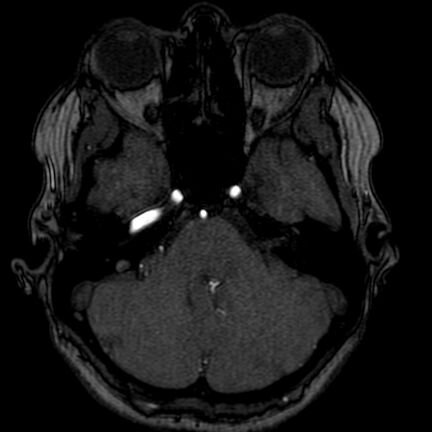

Trying to uncover the structure and functioning of my brain - using MR scans & MindWave device for a performance of this exploration.